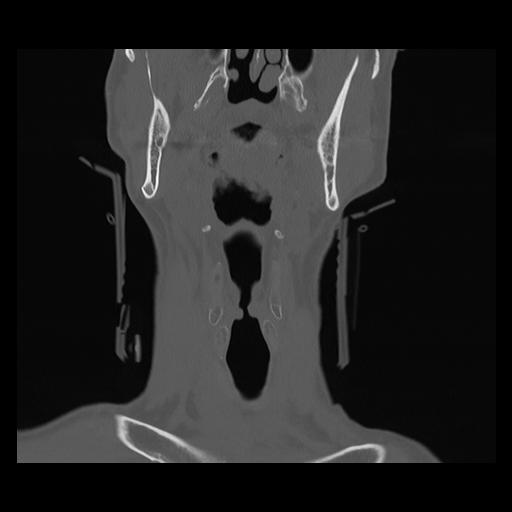

16 HUESO,,Coronal,2.000,HUESO,Coronal,